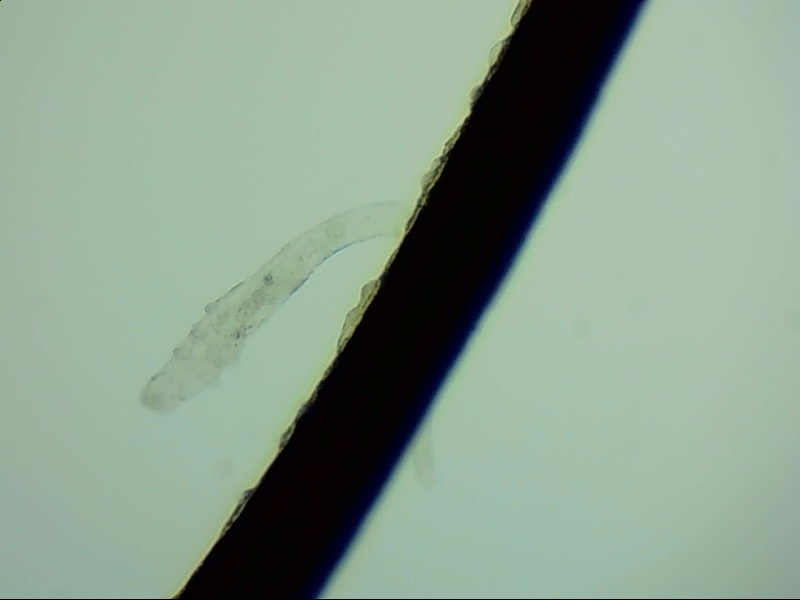

睫毛根部的蠕形螨

蠕形螨是自然界中常見的生物,在人的身上有兩種,分別是毛囊蠕形螨和脂質(zhì)蠕形螨,人身上以毛囊蠕形螨為主,它們主要生活在睫毛根部。

在電子顯微鏡下我們才能看到睫毛根部的一只只蠕形螨,它們不但會啃食睫毛根部附近的油脂,讓睫毛長的東倒西歪,還會給眼睛帶來發(fā)癢、干澀、瞼緣炎充血、在睫毛根部留下袖套狀的分泌物等各種各樣的癥狀,拉低患者的生活質(zhì)量。